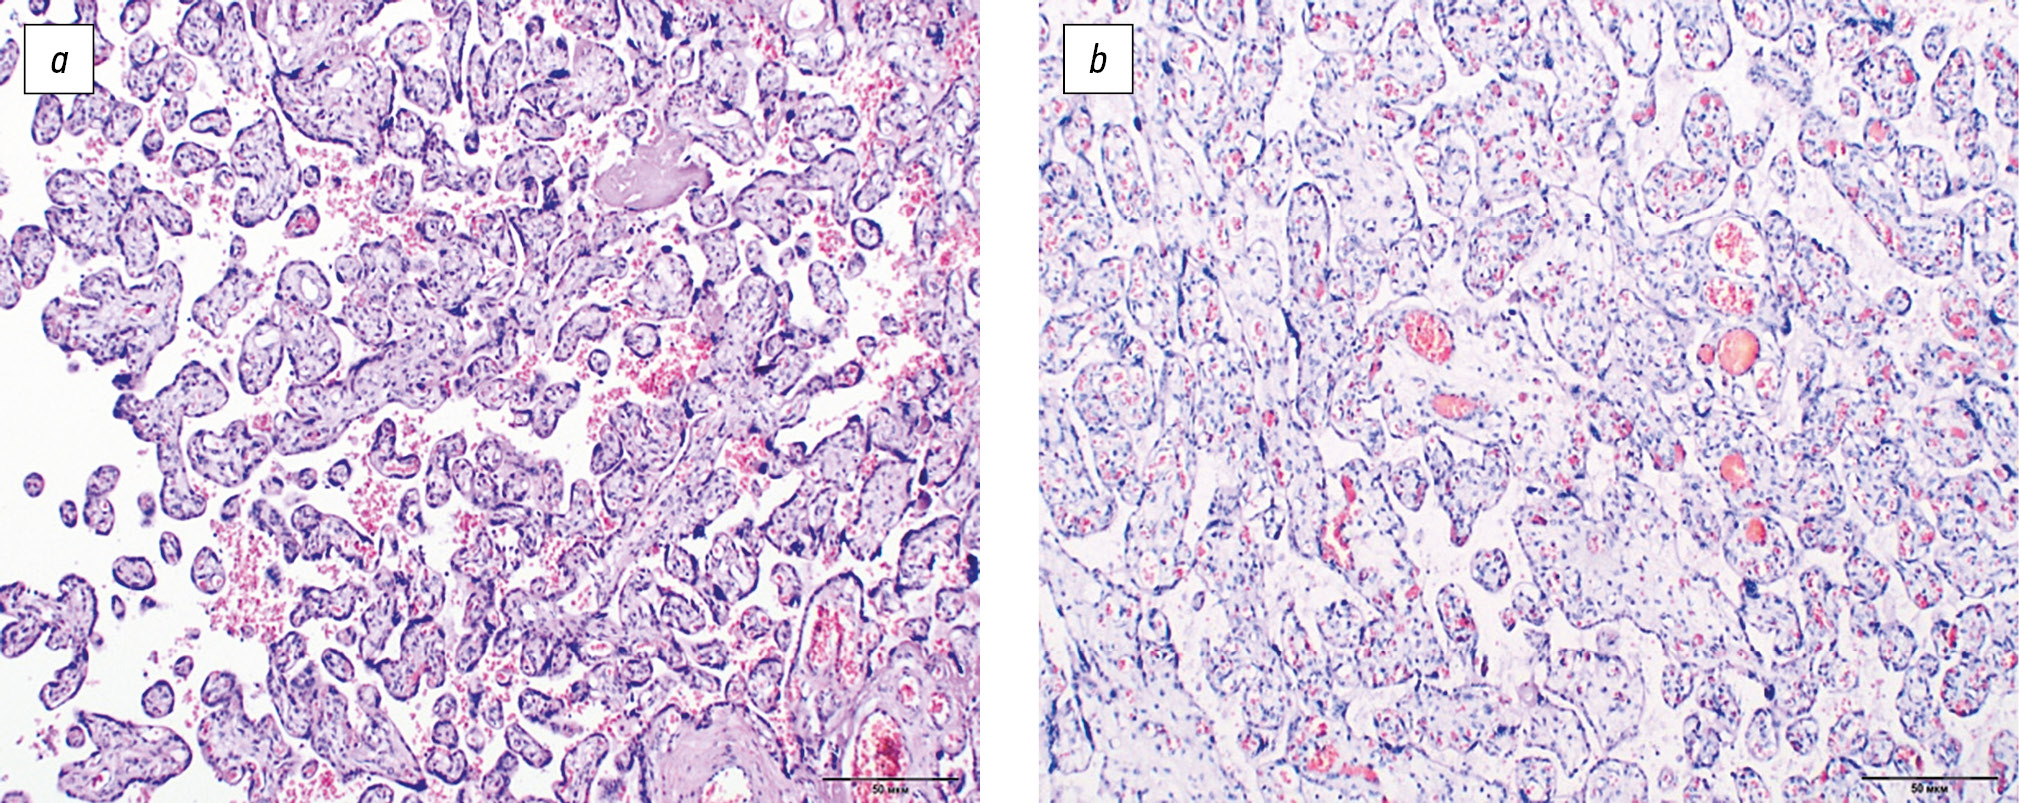

In 14 (77.8%) cases in group 2, placental insufficiency was in the stage of compensation, characterized by moderate plethora and persistence of mature intermediate villi, and in 2 (11.1%) cases, it was in the stage of subcompensation, represented by uneven blood filling of the vascular bed of the villi, plethora of veins of intermediate villi, and relative anemia of terminal chorionic villi (Fig. 1).

Fig. 1. The structure of the villous chorion: (a) terminal type of structure of the villous tree of the placenta at full-term pregnancy (staining with hematoxylin and eosin, ×100); (b) dissociated chronic placental insufficiency (staining with hematoxylin and eosin, ×100)